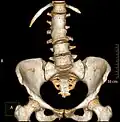

Congenital vertebral anomalies are a collection of malformations of the spine. Most, around 85%, are not clinically significant, but they can cause compression of the spinal cord by deforming the vertebral canal or causing instability. This condition occurs in the womb. Congenital vertebral anomalies include alterations of the shape and number of vertebrae.